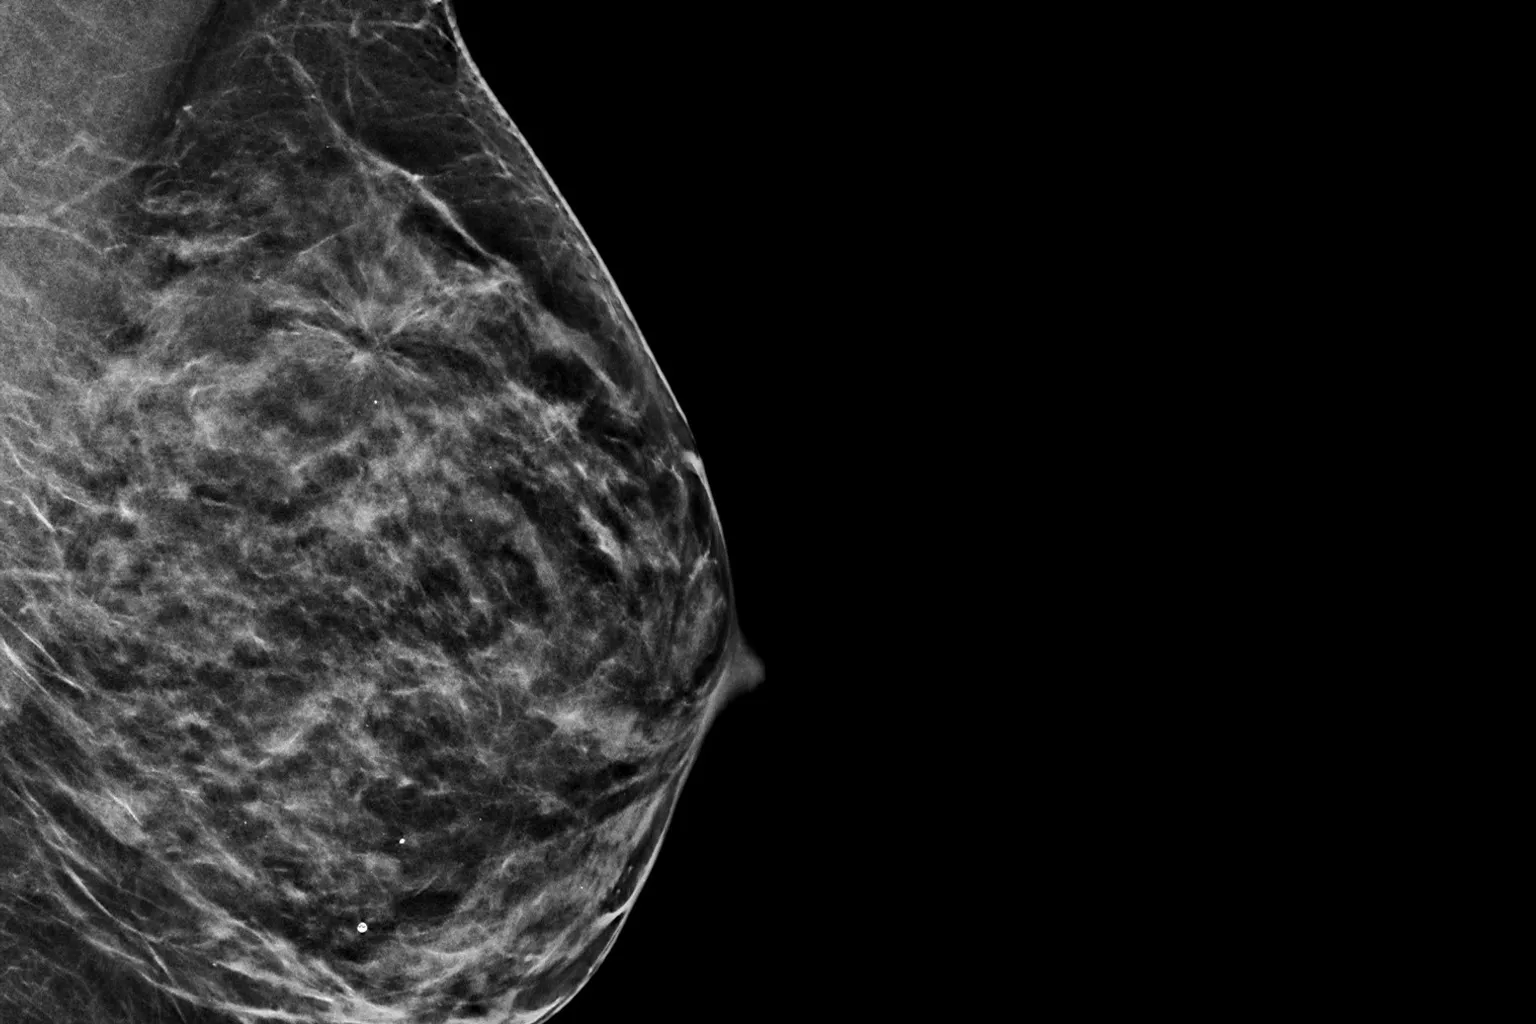

Hologic Selenia® Dimensions, yoğun meme dokusuna sahip kadınlarda bile yüksek çözünürlükte ve detaylı görüntüler sunar. Bu teknoloji, meme dokusunun yoğunluğundan kaynaklanan tanı zorluklarını aşarak, gizli kalabilecek küçük lezyonların tespit edilmesini mümkün kılar. Klinik çalışmalar, bu sistemin yoğun meme dokusunda meme kanseri tespit oranını anlamlı ölçüde artırdığını ve erken teşhiste önemli rol oynadığını göstermektedir. Böylece risk altındaki hastalar için güvenilir ve etkili bir tarama çözümü sağlar.

Modern meme görüntülemede yalnızca iyi görüntü kalitesi yeterli değildir; verilerin doğru, tutarlı ve klinik olarak anlamlı bir şekilde analiz edilmesi de büyük önem taşır. Hologic’in Quantra™ yazılımı, meme yoğunluğunu objektif olarak ölçen ve sınıflandıran gelişmiş bir analiz aracıdır. Quantra, kadınların meme yapısına özel risk sınıflaması ve tarama stratejileri belirlemeye olanak tanır.

Quantra, Amerikan Radyoloji Derneği’nin BI-RADS® yoğunluk kategorilerini temel alır ve dört seviyeli sınıflandırma sunar. Bu sayede manuel değerlendirmelerde görülebilecek subjektif farklılıkları azaltır, tekniker ve radyologlar arasında daha güvenilir bir değerlendirme standardı oluşturur.

Tam entegre yapısıyla Quantra, tarama sürecine zaman kaybettirmeden katkı sağlar. Yoğun meme dokusuna sahip bireylerde ek görüntüleme kararı verirken hızlı ve tutarlı veri sunar; böylece erken tanıda klinik etkinliği destekler.